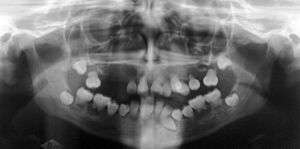

| Preoperative panoramic radiographs showing features of dentin dysplasia type I | |

Type 1: Roots are short, blunt and conical. In deciduous teeth, pulp chambers and root canals are completely obliterated while in permanent they may be crescent shaped.

Type 2: The pulp chamber of the deciduous teeth become completely obliterated. The permanent teeth displays large pulp chamber in the coronal portion of the tooth - referred to as thistle tube appearance. Pulp stones may be found.